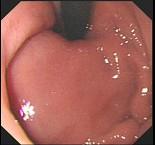

问题 男性,60岁。胃溃疡病史8年,近3月腹痛、腹胀、食欲减退、消瘦明显、粪隐血持续阳性,应用抗酸剂治疗胃痛无效。胃镜检查如图:该病人最可能的诊断是 ( )

选项 A、胃泌素瘤 B、胃溃疡恶变 C、穿透性胃溃疡 D、顽固性溃疡 E、复合溃疡

答案 B